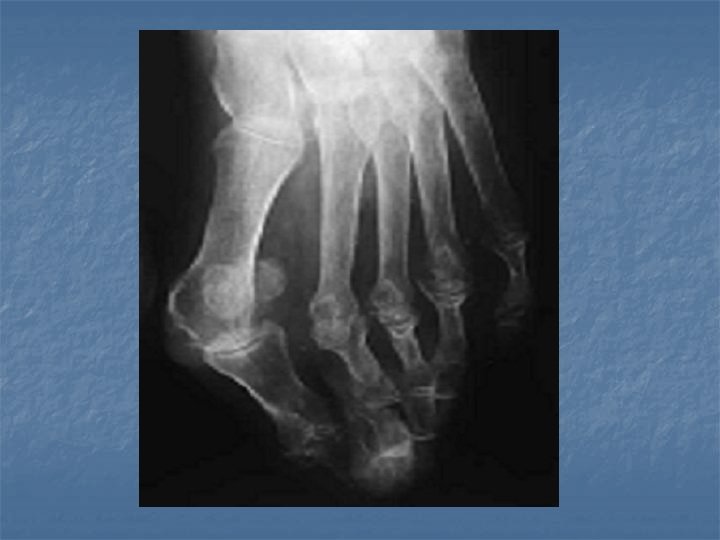

Signes radiologiques diminution rapide de la densité osseuse (ostéodensitométrie) destruction de la membrane synoviale Evolution Maladie chronique évoluant par poussée

Prescription médicale ECG, RP, Bilan radio (pieds, mains, autre suivant les signes cliniques), bilan sanguins (BR n° 1), latex waler rose, FAN (facteurs anti-nucléaires), Ac anti-kératine, sérologies hépatites B, C, HIV (avec accord du patient), aldolase n Traitement : inexium : 1 cp par jour, Méthotrexate, actiskenan 10 mg : 1 à 6 par jour si besoin

Prescription médicale • Les examens : - BR n° 1 le 05/12/08 - Bilan radiologique le 05/12/08 : intense discopathie dégénérative L 4 L 5, L 5 S 1 - Radio pulmonaire le 05/12/08 - Scanner lombaire le 06/12/08 : arthrose inter apophysaire L 4 L 5, à l’étage L 5 S 1 : volumineuse hernie discale gauche au contact du trajet de la racine L 5 gauche.